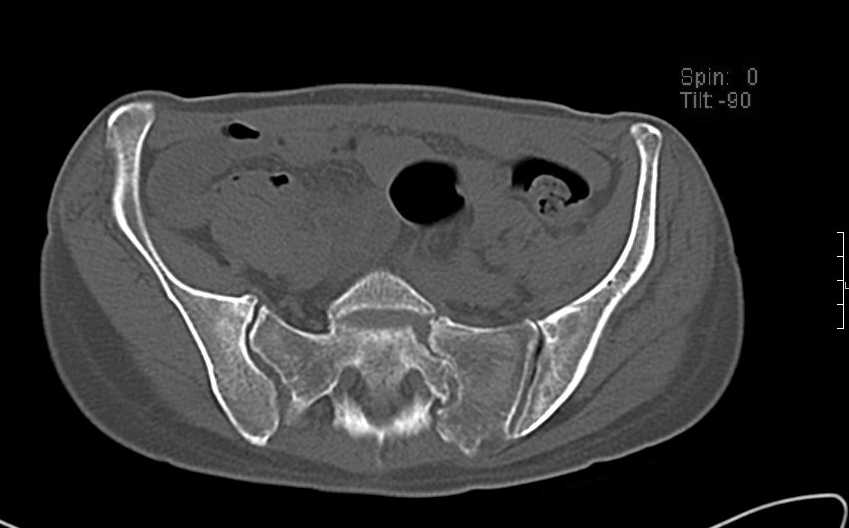

Больная 43 года (промышленный альпинист), 28.07.08 в результате падения с 5 этажа получила политравму: Перелом свода и основания черепа. Вертикально-нестабильное повреждение таза, осложнённое разрывом мочевого пузыря. Чрезвертельный перелом левого бедра. Перелом правой таранной кости, переломовывих правой кубовидной кости. Тупая травма живота, разрыв печени, ушиб почек. Забрюшинная гематома. В день травмы - лапаротомия, ушивание ран печени. Разрыв мочевого пузыря не диагностирован. Течение болезни осложнилось развитием мочевого затёка и обширной пред- и забрюшинной флегмоны, сформировался свищ мочевого пузыря. 19.8.2008 вскрытие, дренировние флегмоны, ревизия мочевого пузыря, обтурация мочевого свища (свищ закрылся в октябре), 1.10.2008 некрэктомия, пластика по Шеде-Лидскому правой кубовидной кости. По результатам КТ диагностирован рак правой почки (диагностическая находка), 8.10.2008 нефрэктомия справа. Переломы велись консервативно. Имеется вертикальное смещение левой половины таза с выраженным отведением крыла (клинически подвижности нет), несросшийся низкий двухколонный перелом левой вертлужной впадины с потерей конгруэнтности, укорочение около5 см, застарелый разрыв лонного сочленения, неправильно сросшиеся переломы обеих ветвей правой лонной кости с укорочением, патологическая подвижность лоно-седалищного фрагмента слева. Правая нижняя конечность неопорна, несмотря на то, что лежа прямую ногу поднимает, ходит на левой ноге (ортопедическая обувь) с костылями, справа тазобедренный ортез. Седалищные нервы работают.Урологи отпустили больную на 6 мес.